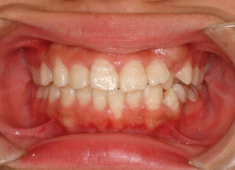

治療前